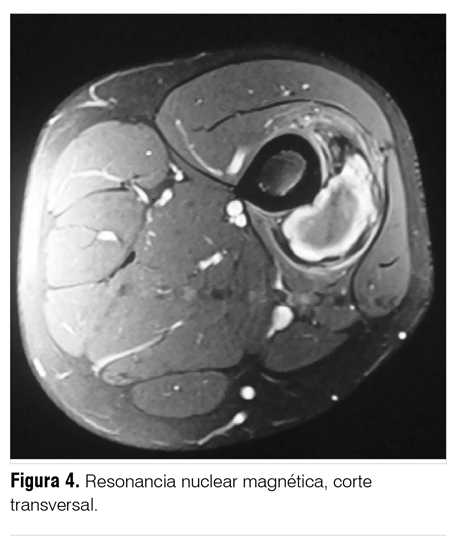

La resonancia nuclear magnética (RNM) identifica a nivel de tercio medio de muslo derecho en proyección del vasto intermedio una formación ovoidea de pared fina y bien delimitada. Su señal es heterogénea en el interior en secuencias T1 y T2, hallazgo compatible con hemoglobina en distintos estadios de evolución. Sus medidas: transversal 6 cm, antero-posterior 4 cm y longitudinal 5 cm (figura 3 y 4).